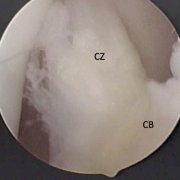

Figure 6A. Knee at 90° flexion, showing the IPP, central body, and portions of the fat pad. The IPP (CZ) is vertical, appears separate and has a leading edge that is straight, suggesting that it is under tension.